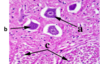

The image shows a transverse section of the cervical spinal cord. The area arrowed at (a) and (b) has been stained to show the grey matter, which resembles a butterfly in shape. What are structures a and b known as ?

a-Dorsal horn

b-Ventral horn

What kinds of nerve fibre will enter the spinal cord at (a)?

Nerve fibres from the Peripheral Nervous System(PNS).

The cell bodies of which type of neurone will be found in (b)?

The ventral horns contains the cell bodies of motor neurons that send axons via the ventral roots of the spinal nerves to terminate on striated muscles.

What are the large, dark blue-staining projections (c) on either side of this section of the spinal cord?

Dorsal root ganglion-Whihc contain cell bodies of sensory neurons which relay information form the periphery to the spinal cord through the dorsal horns.